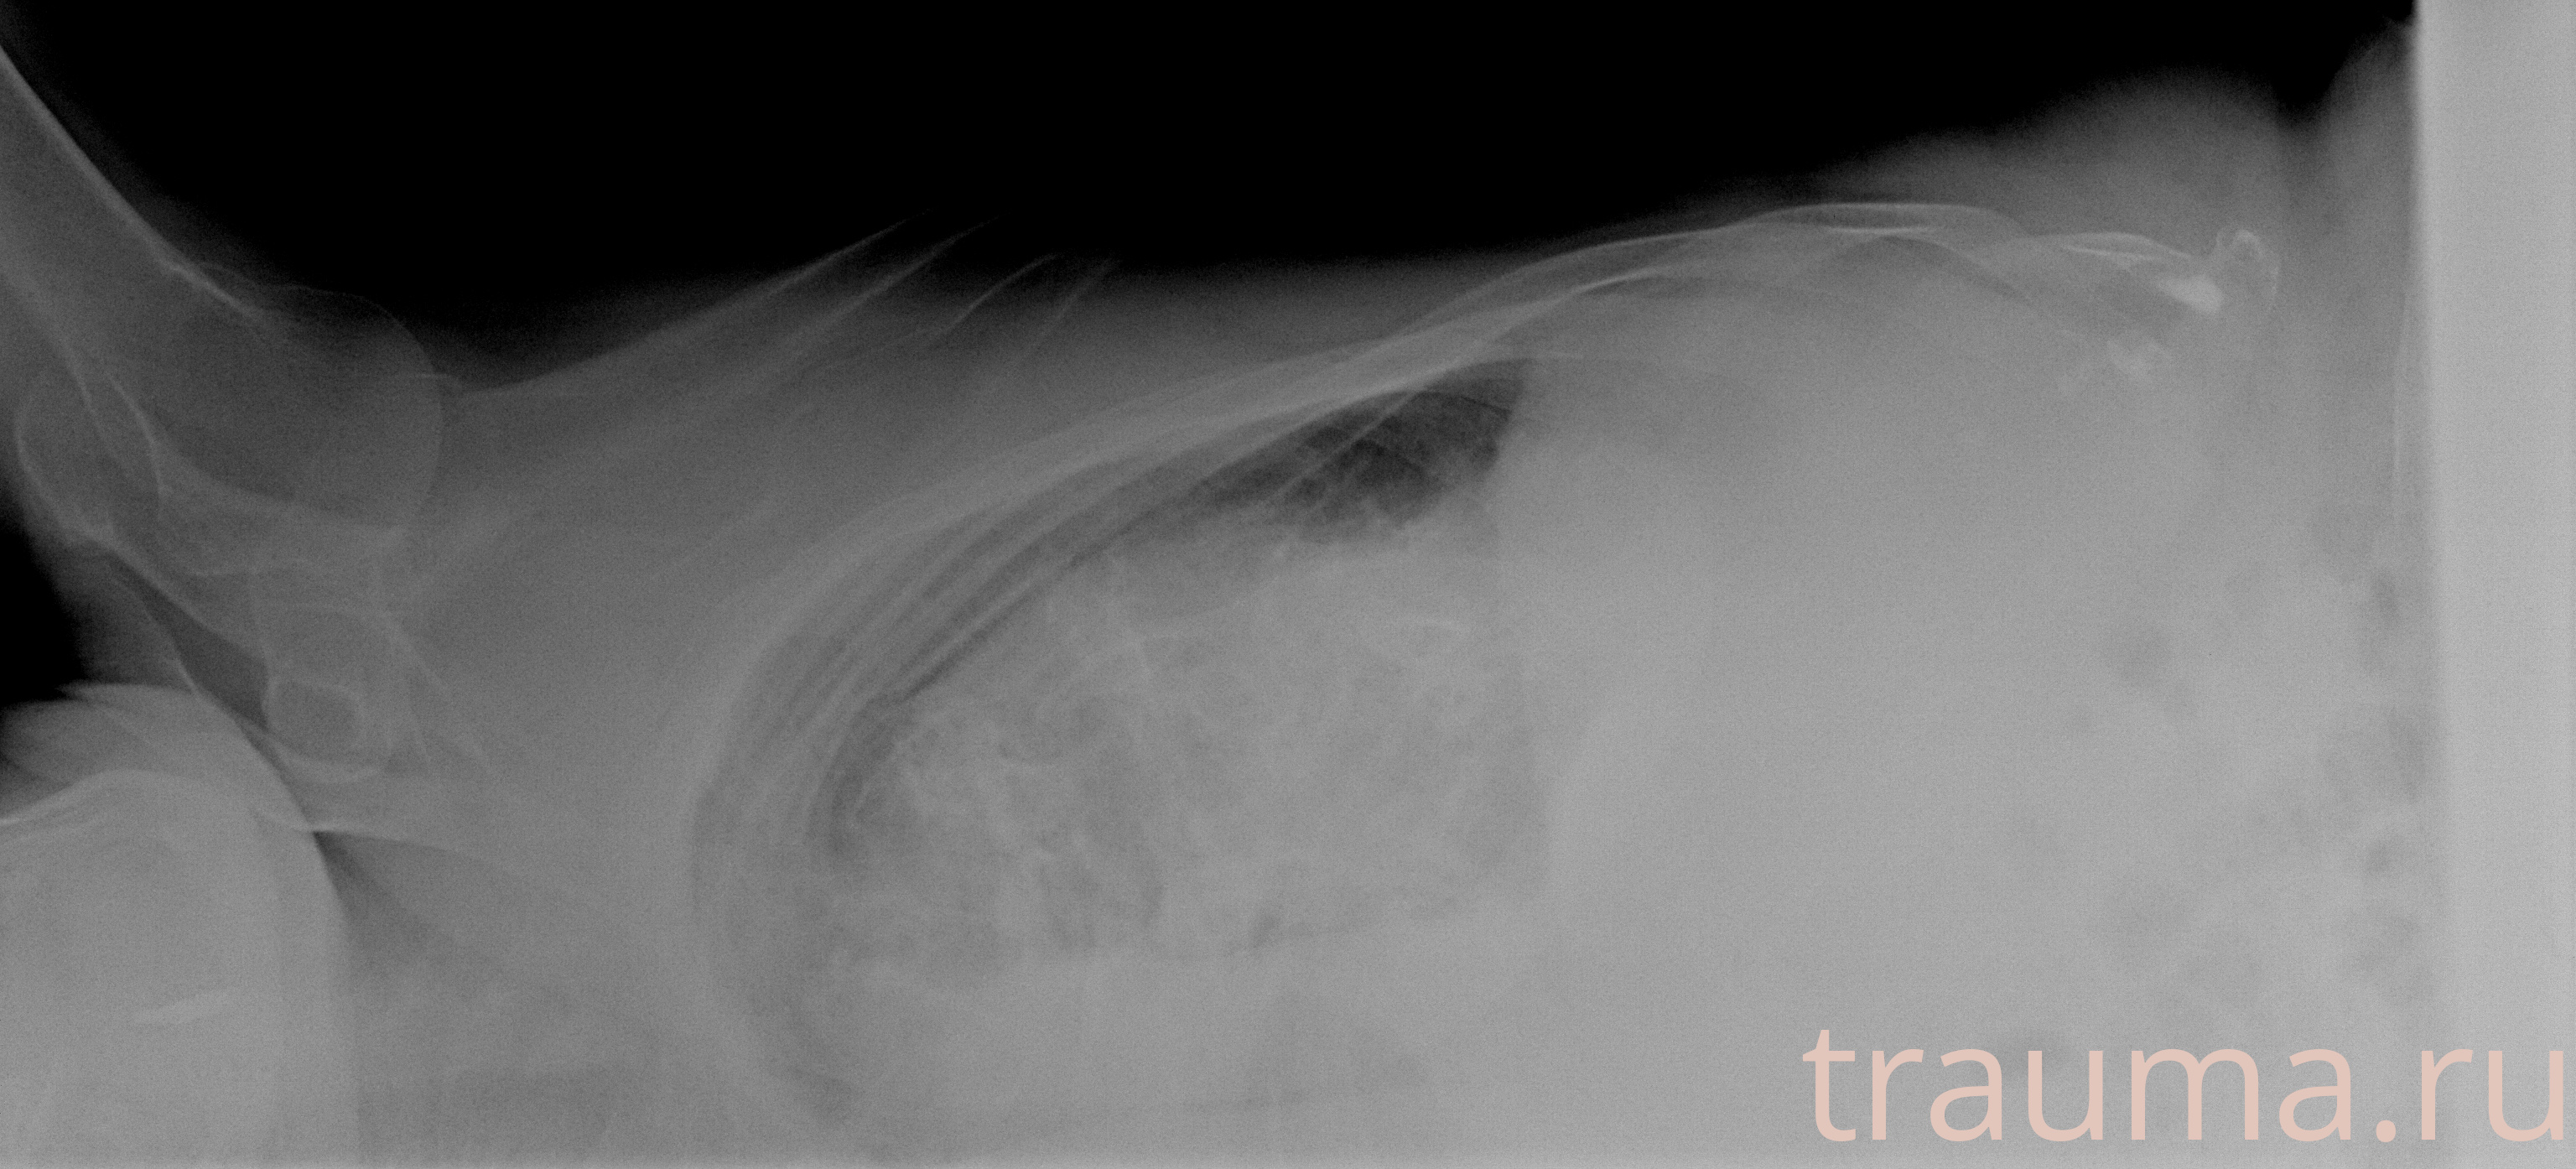

Рентгенограммы

Рентген на дому: по вашему адресу приезжает врач-рентгенолог, травматолог-ортопед с мобильным рентгеновским аппаратом, проводит диагностику травмы или заболевания, делает необходимые рентгенограммы, дает рекомендации по дальнейшему лечению. Получить качественные снимки в домашних условиях возможно благодаря уникальной методике, разработанной МосРентген Центром для института  Склифосовского

при переломе шейки бедра и пневмонии от компании МосРентген Центр - партнера Института имени Склифосовского